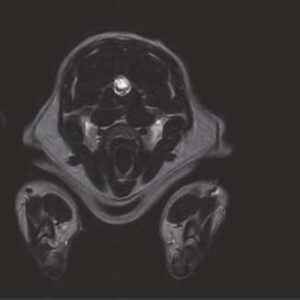

- Image Quality comparable to 1.5T MRI in the market

The PANION PRO comes with the double-pole open magnet design with a wide opening gap of 40 cm to accommodate large-sized animals on an efficient patient handling platform, the strongest gradient amplitude at 33mT/m and slew rate of 90 T/m/s, among all other open MRI systems, resulting in high spatial resolution of images in short scan time. The 6-direction patient table permits iso-centre imaging of all anatomical regions.

Clinical Images